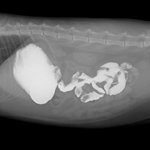

- 조영 검사

- 소화기 조영검사: 뼈나 금속과 같은 단단한 이물이 아니거나 이물로 인한 소화기계의 폐색이 심각하지 않은 경우에는 단순한 방사선 검사만으로 정확한 진단을 내리기 어렵습니다. 이러한 상황에서는 조영 검사를 진행하고 있으며, 식도, 위, 소장, 대장 내 이물, 파열, 협착, 폐색을 검사하고 있습니다.

비뇨기 조영 검사: 신장 기능에 이상이 있거나 요관의 폐색이 의심되는 경우 배설성 요로 조영술을 통해 신장 기능을 평가합니다. 이를 통해 수술적 제거뿐만 아니라 향후 내과적 치료방향에 대해 좀 더 정확한 정보를 얻을 수 있습니다. 방광 내 종양, 결석, 요도 파열이나 폐색이 의심되는 환자에서는 역행성 요로 조영술을 실시합니다.